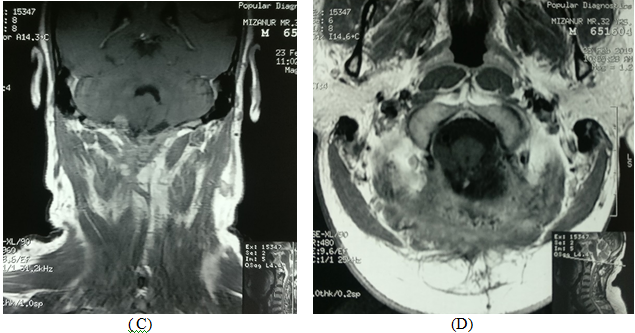

A 34years male admitted in our Department of Neurosurgery with the complaints of neck pain for 2year, progressive weakness of all limbs in the form of rotating paralysis starting with left upper limb followed by left lower limb, right lower limb & right upper limb for 15months without bowel bladder disturbance. On neurological examinations patients was found to be quadriparetic having muscle power MRC grade 3 on both side rendering her gait to be hemiplegic and walk with support. All her deep tendon reflexes were exaggerated. Hoffman sign was positive bilaterally.  Planters were bilaterally extensor. Ankle clonus was present bilaterally. He did not have any hypo or hyper pigmented patch in any part of the body. MRI of brain & cervical spine showed an intra-dural extra medullary lesion measuring about 5 x 3.5cm at foramen magnum extending both up and down situated posteriorly more on left side (Figures 4A-C). There was no other lesion on further cranial & spinal screening MRI.

Figure 4MRI of brain & cervical spine showed an intra-dural extra medullary lesion measuring about 5 x 3.5 cm at foramen magnum extending both up and down situated posteriorly more on left side.